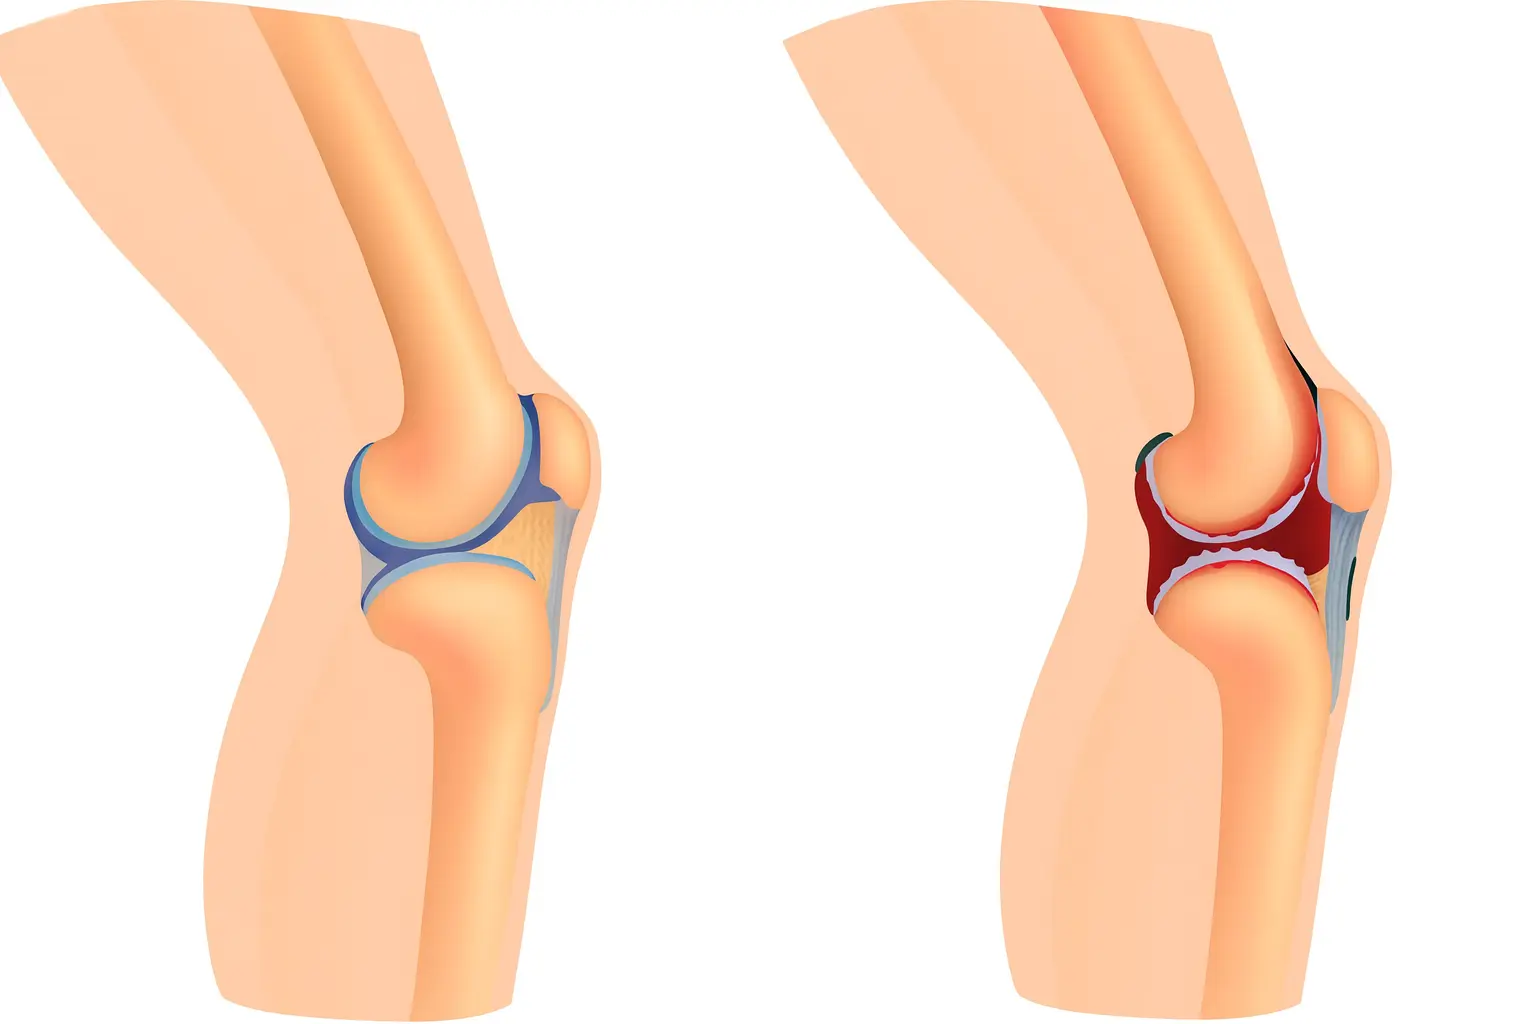

Стадии серонегативного ревматоидного артрита

Состояние развивается поступательно. Каждая стадия отражает глубину воспаления и степень изменения суставных тканей, сроки усредненные:

- Начальная стадия. Воспаление затрагивает синовиальную оболочку. Боль умеренная, скованность появляется после отдыха. Рентген чаще без изменений.

- Развернутая стадия. Появляется отек, ухудшается подвижность, на снимках видна узурация краев суставной поверхности.

- Прогрессирующая стадия. Сустав деформируется, движения ограничиваются, человеку сложнее выполнять бытовые задачи.

- Поздняя стадия. Формируются стойкие изменения. Подвижность резко снижена. Требуется длительная терапия, реабилитация.

При раннем начале базисной терапии прогрессирование можно существенно замедлить, а у части пациентов – остановить развитие эрозий и деформаций.

Суставные осложнения:

- Эрозии, разрушение хряща. Постоянное воспаление истончает суставные поверхности, уменьшая подвижность.

- Деформации. Изменение оси пальцев, отклонение кисти, нарушение механики шага.

- Анкилоз. Сустав утрачивает подвижность из-за сращения тканей.

- Хроническая нестабильность. Связки теряют прочность, движения становятся болезненными и неточными.